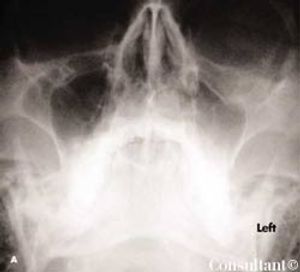

Four hours before he arrived at the emergency department, a 33-year-old man had been struck in the face by a rock. A laceration and periorbital hematoma were noted on the left side of the patient’s face. He complained of pain in this area. There was no history of intraocular disease. The left globe was intact, and no neurologic deficit was found.